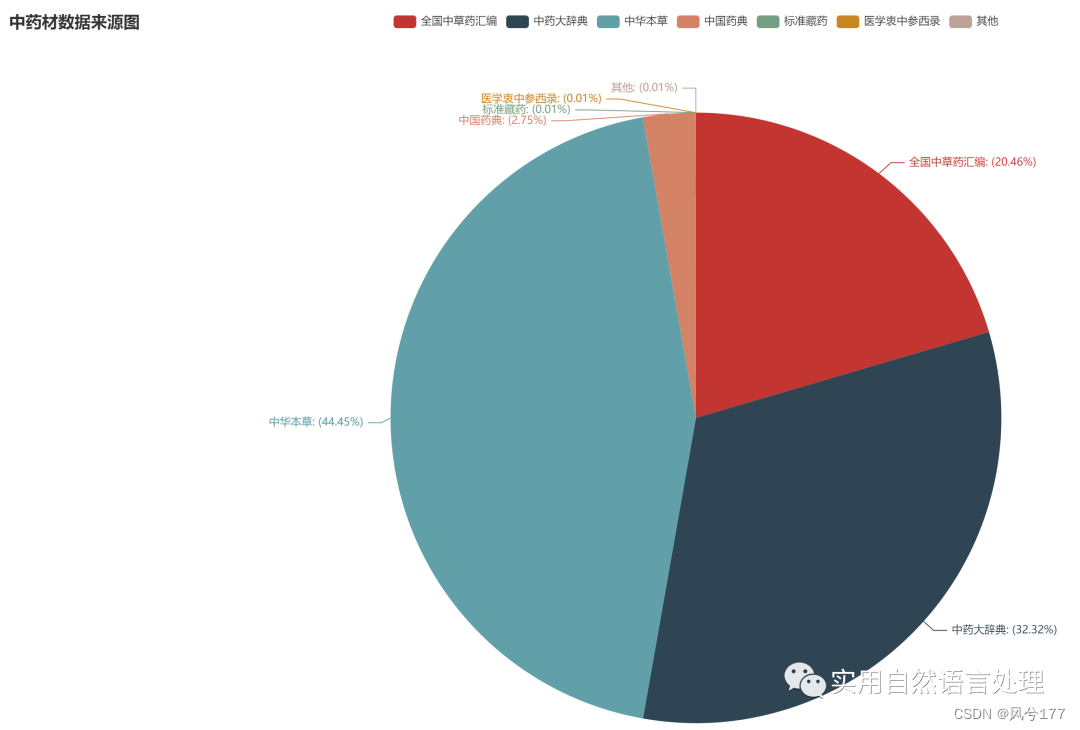

2.3 中药材知识图谱分析结果可视化

(2)中药材来源数据可视化